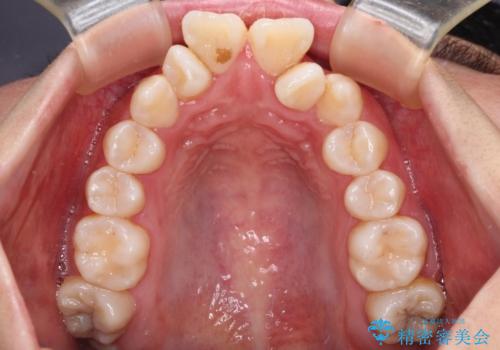

- 飛び出した上顎の前歯と八重歯を気にして来院された患者様です。

口元を積極的に引っ込めるために、上下左右の小臼歯計4本を抜歯することとしました。

下顎前歯の歯肉が元々薄く、歯肉退縮リスクがあったため、細心の注意を払って治療を進めましたが、残念ながら1歯退縮を起こして歯根が露出してしまいました。

今後、患者様と相談しながら、歯肉移植を行っていく予定です。